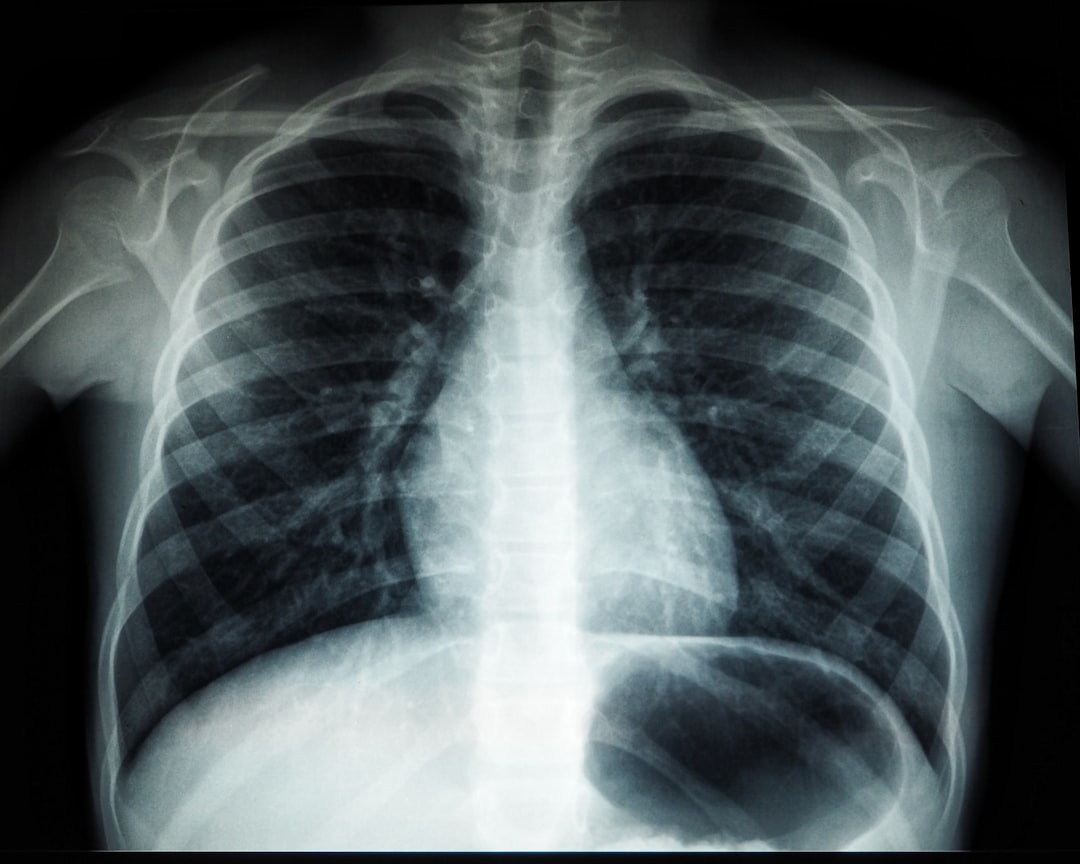

기관지염은 호흡기에 발생하는 염증 상태로, 여러 증상이 동반됩니다. 흔히 기침, 가래, 흉통, 호흡 곤란 등이 있습니다. 특히 기관지염 증상 중 기침이 가장 두드러지며, 초기에는 마른 기침이 나다가 점차 가래가 섞인 기침으로 변합니다. 이 때문에 기관지염을 앓고 있는 사람은 일상 생활에서 큰 불편을 겪곤 하죠. 기침이 잦아지면 주변 사람들의 시선도 걱정되기 마련입니다.